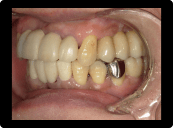

歯周病の治療例

奥歯の重度歯周病は保存困難のため抜歯してインプラント治療。残す歯は歯周病中等度であったため、歯周基本治療歯周外科治療を含めて行い、歯茎からの出血などはなくなった。

BEFORE

AFTER

症例概要

年代・性別

50代 女性

主訴

全体の歯茎から出血する、奥歯が揺れて噛めないことを主訴に来院されました。

治療内容

全顎歯周外科治療(保険治療)+奥歯インプラント治療4本

治療期間

6ヶ月

治療のリスク

歯肉退縮のリスクがあります

治療費用

約160万円